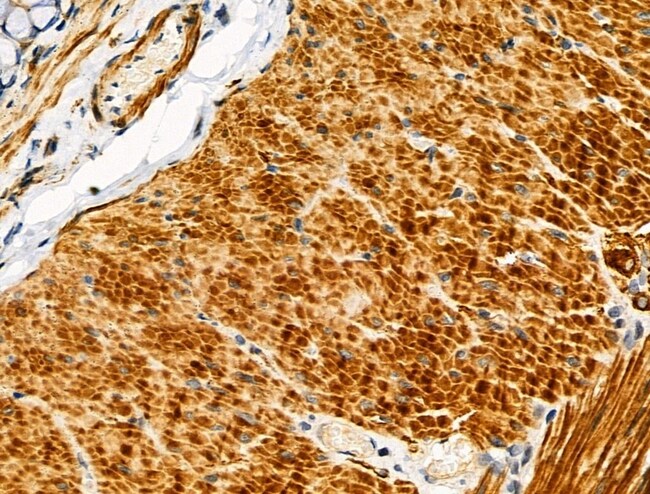

Invitrogen™ CYR61 Polyclonal Antibody

Antibody detects endogenous levels of total CYR61/CCN1.

| Immunohistochemistry (Paraffin), Western Blot, Immunocytochemistry | |